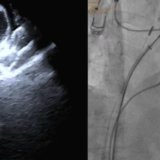

手术在导管室、麻醉科、超声科等多科室协作下进行。团队经股静脉穿刺,在三维标测系统引导下完成房颤射频消融,随后在X线及心腔内超声指导下植入左心耳封堵伞,成功闭合左心耳开口。整台手术历时约两小时,患者房颤转复为正常窦性心律,术后恢复良好,胸闷、心悸症状明显改善。